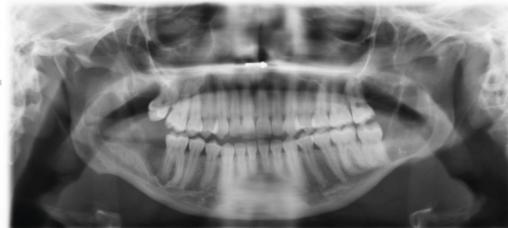

Cette femme de 26 ans consultait pour des douleurs récidivantes au niveau des dents de sagesse. Elle avait comme antécédents un asthme et une néphrectomie du rein droit en raison d’une dysplasie. Sa consommation tabagique était estimée à 6 paquets-année. Le panoramique dentaire (fig. 1 ) montrait quatre images radioclaires entourant les dents de sagesse. La patiente était alors adressée dans le service de chirurgie où un Cone Beam (fig. 2 et 3 ) permettait d’évaluer la taille des lésions kystiques ainsi que leurs rapports avec les structures anatomiques voisines. L’avulsion des dents de sagesse et l’énucléation des kystes étaient réalisées. L’examen anatomopathologique des lésions notait une paroi kystique bordée par un épithélium malpighien ortho- ou parakératosique avec une hyperplasie des couches basales compatible avec des kératokystes bénins odontogènes.